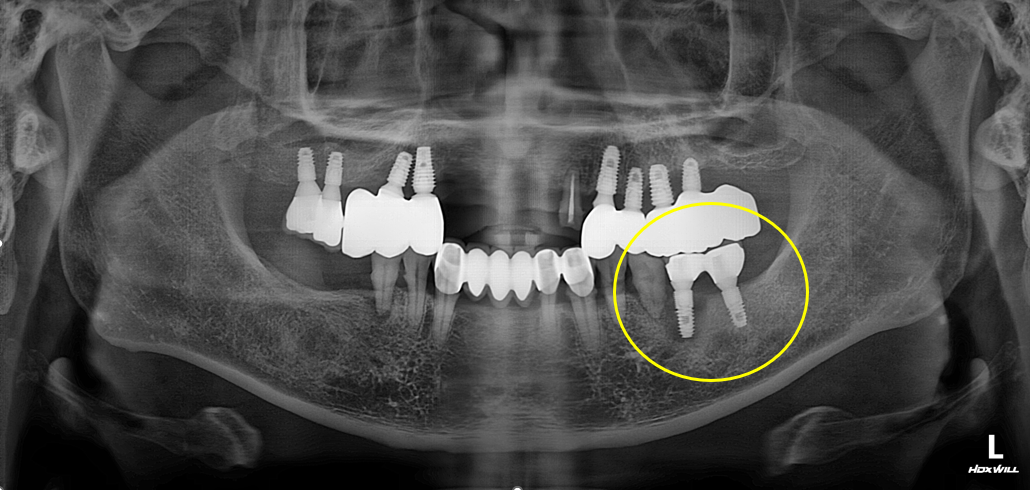

[임플란트] 타치과 임플란트 실패 후 재식립 사례

임플란트 주위 뼈가 녹았거나 임플란트 자체가 파손된 경우도 있습니다.

반대로 임플란트 주변 뼈가 심하게 녹았거나 나사가 부러진 경우에는 살리기보다 제거와 재수술이 더 안전할 수 있습니다.

씹을 때 임플란트가 흔들리거나, 엑스레이 상에서 뼈가 많이 녹아 있는 것이 확인될 때에도 추가 치료 또는 재수술이 필요할 수 있습니다.